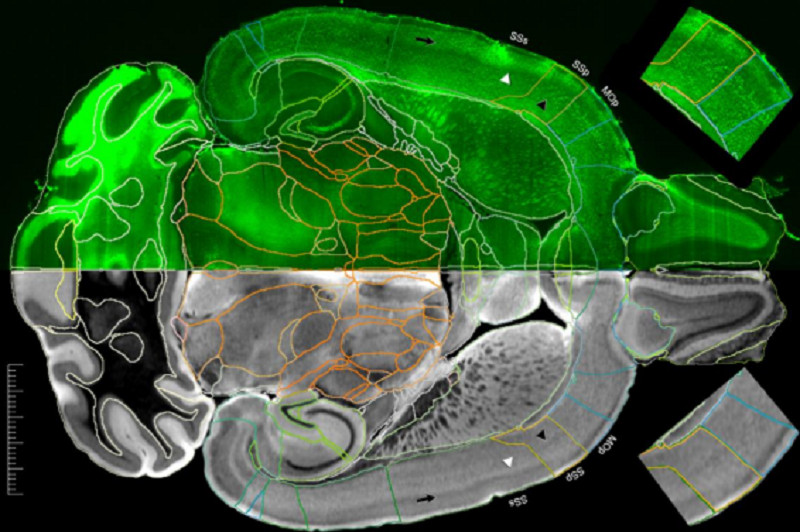

Американские ученые заявили, что смогли получить самые подробные изображения МРТ мозга мыши за всю историю исследований. По их словам, разрешение этих изображений в 27 тысяч раз превышает качество предыдущих.

Группа ученых из разных американских университетов опубликовала в журнале Proceedings of the National Academy of Sciences результаты исследования и рассказали, как добились самого подробного МРТ-изображения мозга грызунов за всю историю наблюдений.

С годами мощности аппаратов увеличивались, но их все еще было недостаточно для того, чтобы разглядеть самые крохотные детали строения органа и выявить патологические новообразования. Но теперь, благодаря высокому угловому разрешению, исследователи получили самые подробные из когда-либо созданных карт МРТ-соединений. И сейчас это гиперреалистичные изображения мозга.

«Изображения тензора диффузии с пространственным разрешением 15 мкм в тысячу раз превышают разрешение большинства доклинических МРТ грызунов. А изображения плотности дорожек со сверхвысоким разрешением в 27 тысяч раз превышают типичные доклинические изображения МРТ», — рассказал Дж. Аллан Джонсон, профессор радиологии Университета Чарльза Путмана, директор Центра микроскопии in vivo при Университете Дьюка.